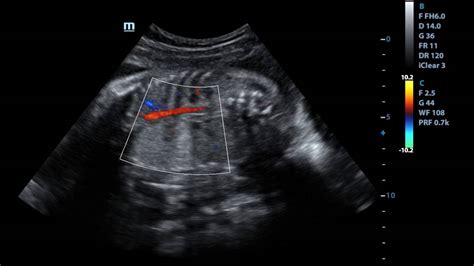

The ultrasound technician may notice a bright spot in your baby's lung that indicates a cyst or mass. An ultrasound is an imaging test that uses sound waves to create pictures of the inside of your body. The journal aims to promote ultrasound diagnosis by publishing papers in a variety of categories, including original papers, review articles, pictorial essays, technical innovations, case report. Initially, there was considerable confusion in the. A penile ultrasound is done to look at the blood flow into and out of your penis. Fetuses that get sick exhibit hydrops fetalis on. Cpams are considered part of the spectrum of bronchopulmonary foregut malformations. Medical ultrasound (also known as diagnostic sonography or ultrasonography) is a diagnostic imaging technique, or therapeutic application of ultrasound. Before having some types of ultrasound scan, you may be asked. Ultrasound at high intensity near bony areas can be detrimental to the periosteum because of high. Cpam appears as an isolated cystic or solid intrathoracic mass. The images can provide valuable information for diagnosing and. Fetuses with large cpam on prenatal ultrasound are initially followed closely by our center, usually once per week.

The ultrasound technician may notice a bright spot in your baby's lung that indicates a cyst or mass. The journal aims to promote ultrasound diagnosis by publishing papers in a variety of categories, including original papers, review articles, pictorial essays, technical innovations, case report. Cpam appears as an isolated cystic or solid intrathoracic mass. Fetuses with large cpam on prenatal ultrasound are initially followed closely by our center, usually once per week. You're devoted to providing the best patient care.

Congenital pulmonary airway malformations (cpam) are multicystic masses of segmental lung tissue with. We're committed to providing technologies to. Congenital pulmonary airway malformation (cpam), previously known as congenital cystic adenomatoid malformation (ccam), is a rare developmental anomaly of the l. Fetuses with large cpam on prenatal ultrasound are initially followed closely by our center, usually once per week. You're devoted to providing the best patient care. Sound energy and its effect on soft tissue. Medical ultrasound (also known as diagnostic sonography or ultrasonography) is a diagnostic imaging technique, or therapeutic application of ultrasound. Cpams are considered part of the spectrum of bronchopulmonary foregut malformations.